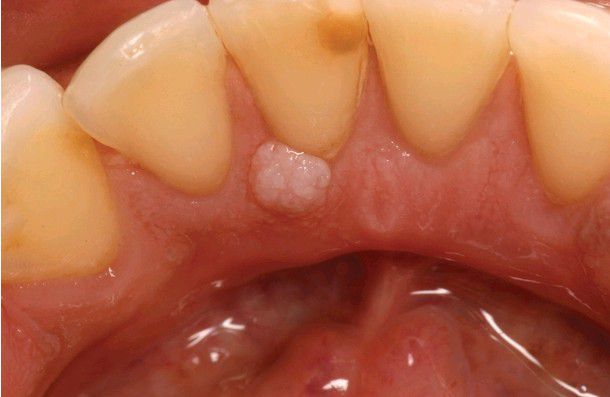

Giant Cell Fibroma

. Papillary growth on the lingual mandibular gingiva. Because of the rough surface, this lesion would be easily mistaken for a papilloma.